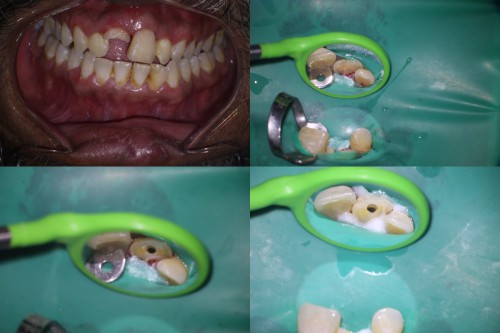

#18 RCT

By Reuben Joseph / September 5, 2018

#18 RCT With this kind of gingiva sinking the whole tooth an indirect post-endo would […]